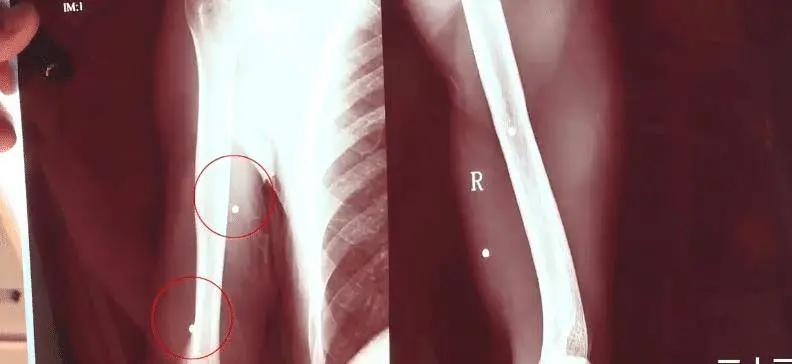

11月1日,湖南南县一名男子夜间垂钓时,为躲避巡查暂躲草丛,不料被4名非法狩猎者误认成猎物,遭改装火药枪击中脑部。目前伤者仍在ICU抢救,医疗费已超20万元。案发后,警方迅速控制4名涉案人员,案件已移交刑侦部门,枪支来源等细节正进一步调查。